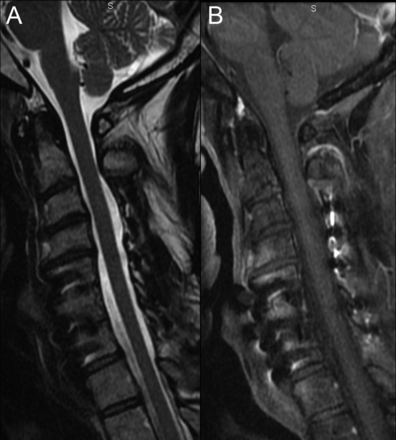

一个44岁的男人提供2周的进步对身体麻木,软弱,圆周烧灼感在他的躯干。脊柱MRI显示纵向广泛脊髓炎(图1)。MRI大脑和实验室调查除了脑脊液淋巴细胞是正常脑脊液细胞增多(9白细胞/毫米3)。CT显示肺门和纵隔淋巴结病,活检显示noncaseating肉芽肿结节病的暗示。作为病人有多个临床复发类固醇,他与英夫利昔单抗治疗输液(5毫克/公斤每4周),而且有完整的临床和放射分辨率后1年(图2)。脊髓炎呈现结节病的特点是非常罕见的,对英夫利昔单抗。1,2

图1

预处理核磁共振

矢状t2加权图像(一)演示了支流hyperintensity从上部颈椎脊髓胸上。在postgadolinium t1加权图像(B),增强多焦点的,不完整的。